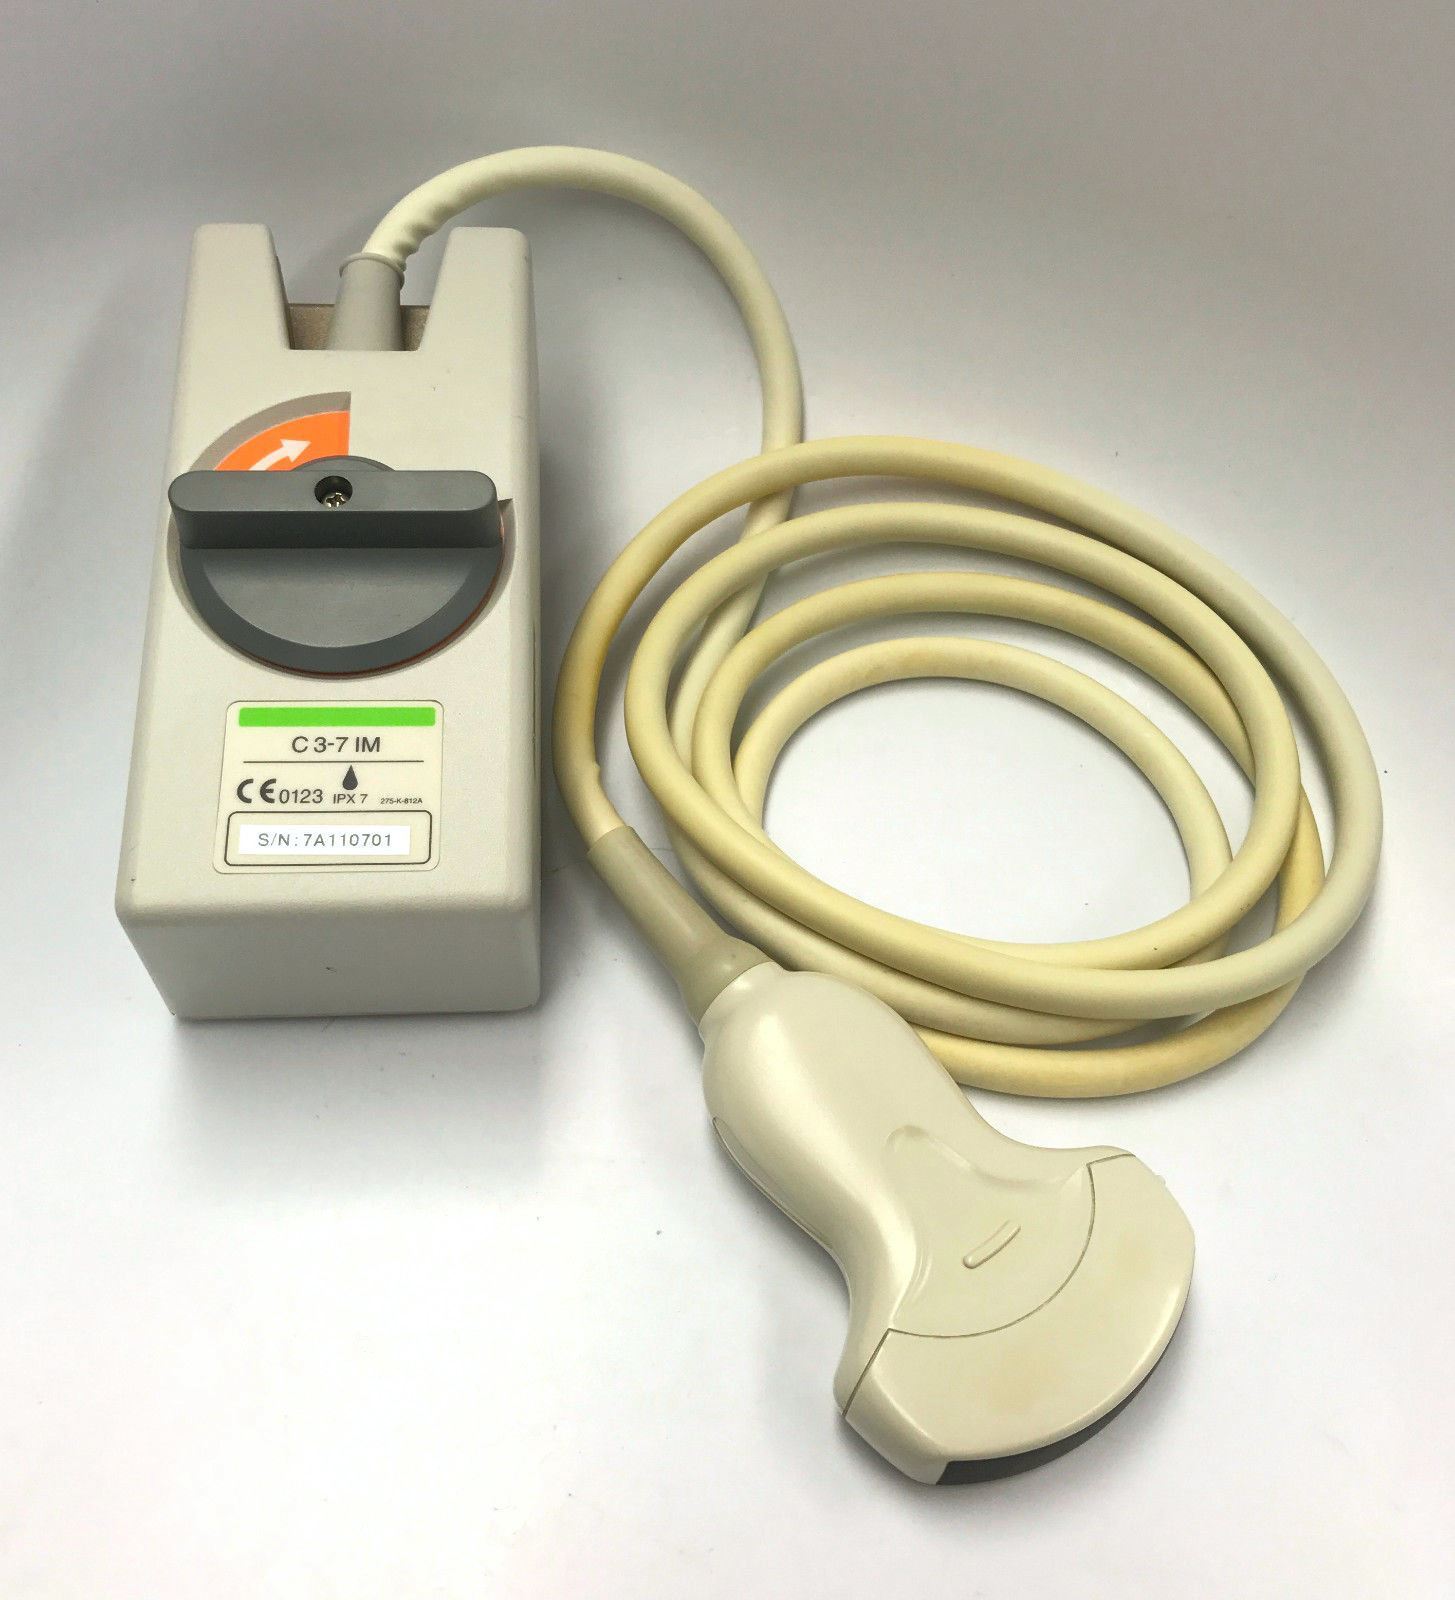

DIAGNOSTIC ULTRASOUND MACHINES FOR SALE

Samsung Medison Accuvix XG with 3D/4D convex probe

Sale price$ 47,965.06